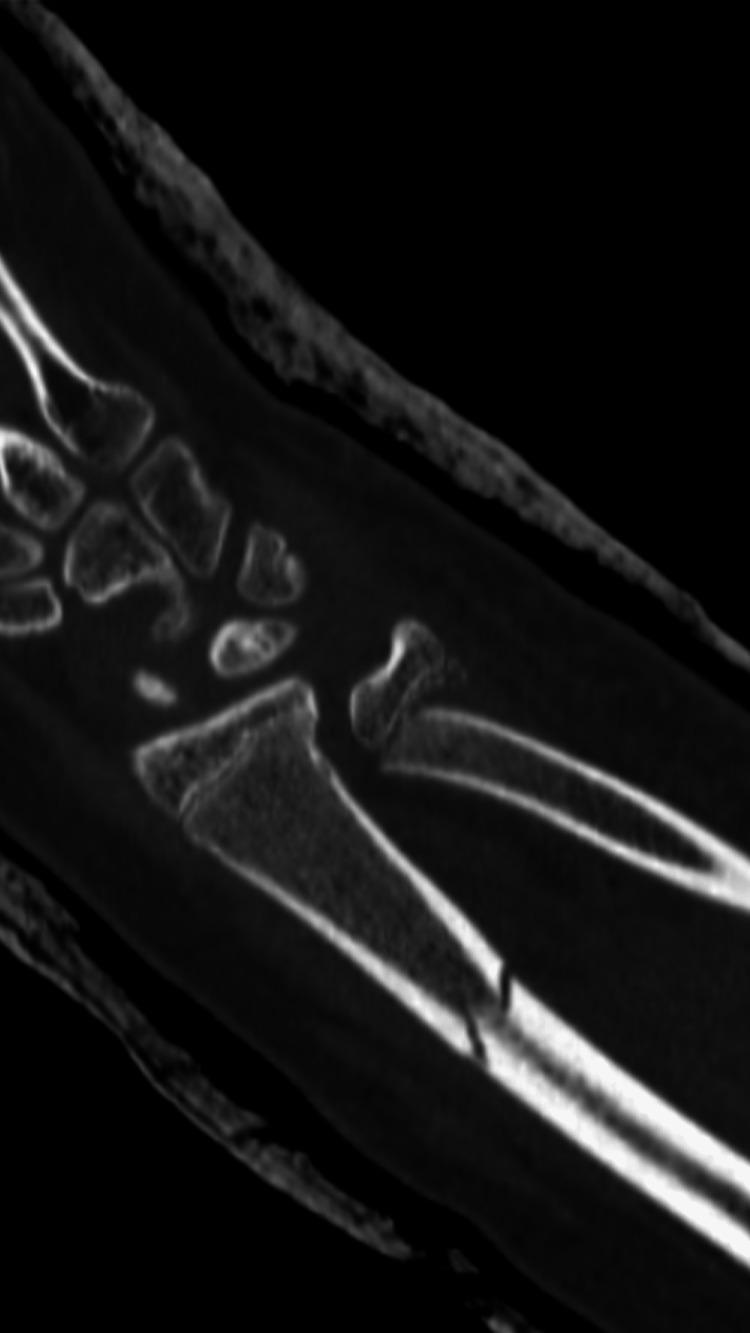

Fractures of the forearm are common among children and adolescents. Radial shaft fracture with dislocation of the distal radioulnar joint (DRUJ), called Galeazzi fracture, is unusual in pediatrics. The Galeazzi-equivalent fracture is a variant of the classic Galeazzi fracture that occurs in children and adolescents. It is a radius fracture associated with a distal ulnar displaced physeal injury without dislocation of the DRUJ. Our patient was a male, aged 15 years, who visited our emergency department after falling off a scooter onto his left hand. Left wrist X-rays showed a displaced Galeazzi-equivalent fracture. After a trial of close reduction, an X-ray showed a displaced and unstable fracture pattern. The patient was subsequently hospitalized for surgical intervention. Open reduction and internal fixation (ORIF) with a plate and screw were used for the radius fracture. The ulna fracture was irreducible; therefore, ORIF with two crossed smooth Kirschner wires (K-wires) was performed. Complete bone union was achieved, and he had a normal range of motion six months postoperatively. The patient is now able to perform daily and sports activities. At two-year follow-up, complications such as DRUJ instability or joint deformity did not occur. In conclusion, open reduction is desired for patients with malalignment or older patients who have a lower potential for sufficient bone remodeling. Regular serial follow-up sessions are required to assess growth arrest and the occurrence of other complications.

前臂骨折在儿童和青少年中很常见。桡骨干骨折合并下尺桡关节(DRUJ)脱位,即盖氏骨折,在儿科中并不常见。类盖氏骨折是经典盖氏骨折的一种变体,发生于儿童和青少年。它是一种桡骨骨折,伴有尺骨远端骨骺移位损伤,而DRUJ无脱位。我们的患者是一名15岁男性,骑滑板车时左手着地后前来我院急诊科就诊。左手腕X线片显示为移位的类盖氏骨折。试行闭合复位后,X线片显示骨折移位且不稳定。患者随后住院接受手术治疗。桡骨骨折采用钢板螺钉切开复位内固定(ORIF)。尺骨骨折无法复位;因此,采用两根交叉光滑克氏针(K针)进行ORIF。术后6个月实现了完全骨愈合,患者活动范围正常。患者现在能够进行日常和体育活动。在两年的随访中,未出现DRUJ不稳定或关节畸形等并发症。总之,对于骨折对位不良的患者或骨重塑潜力较低的年长患者,需要进行切开复位。需要定期进行系列随访,以评估生长停滞和其他并发症的发生情况。